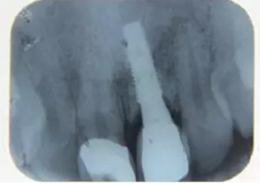

種植完成

種植完成后可以通過拍攝曲面體層或是根尖片來確認種植體的植入情況,并作為資料加以保存。

圖7 曲面體層片